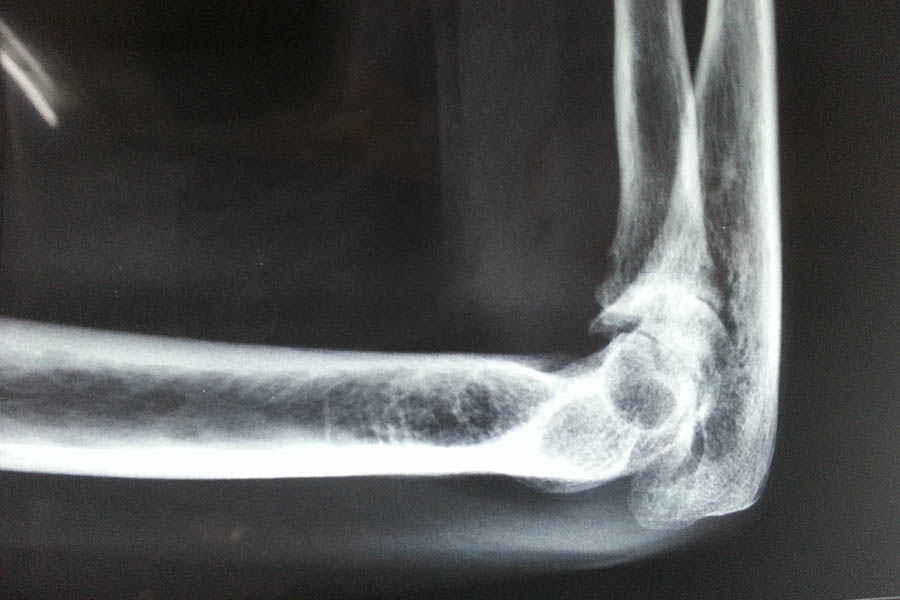

Total Elbow Replacement

Case 1